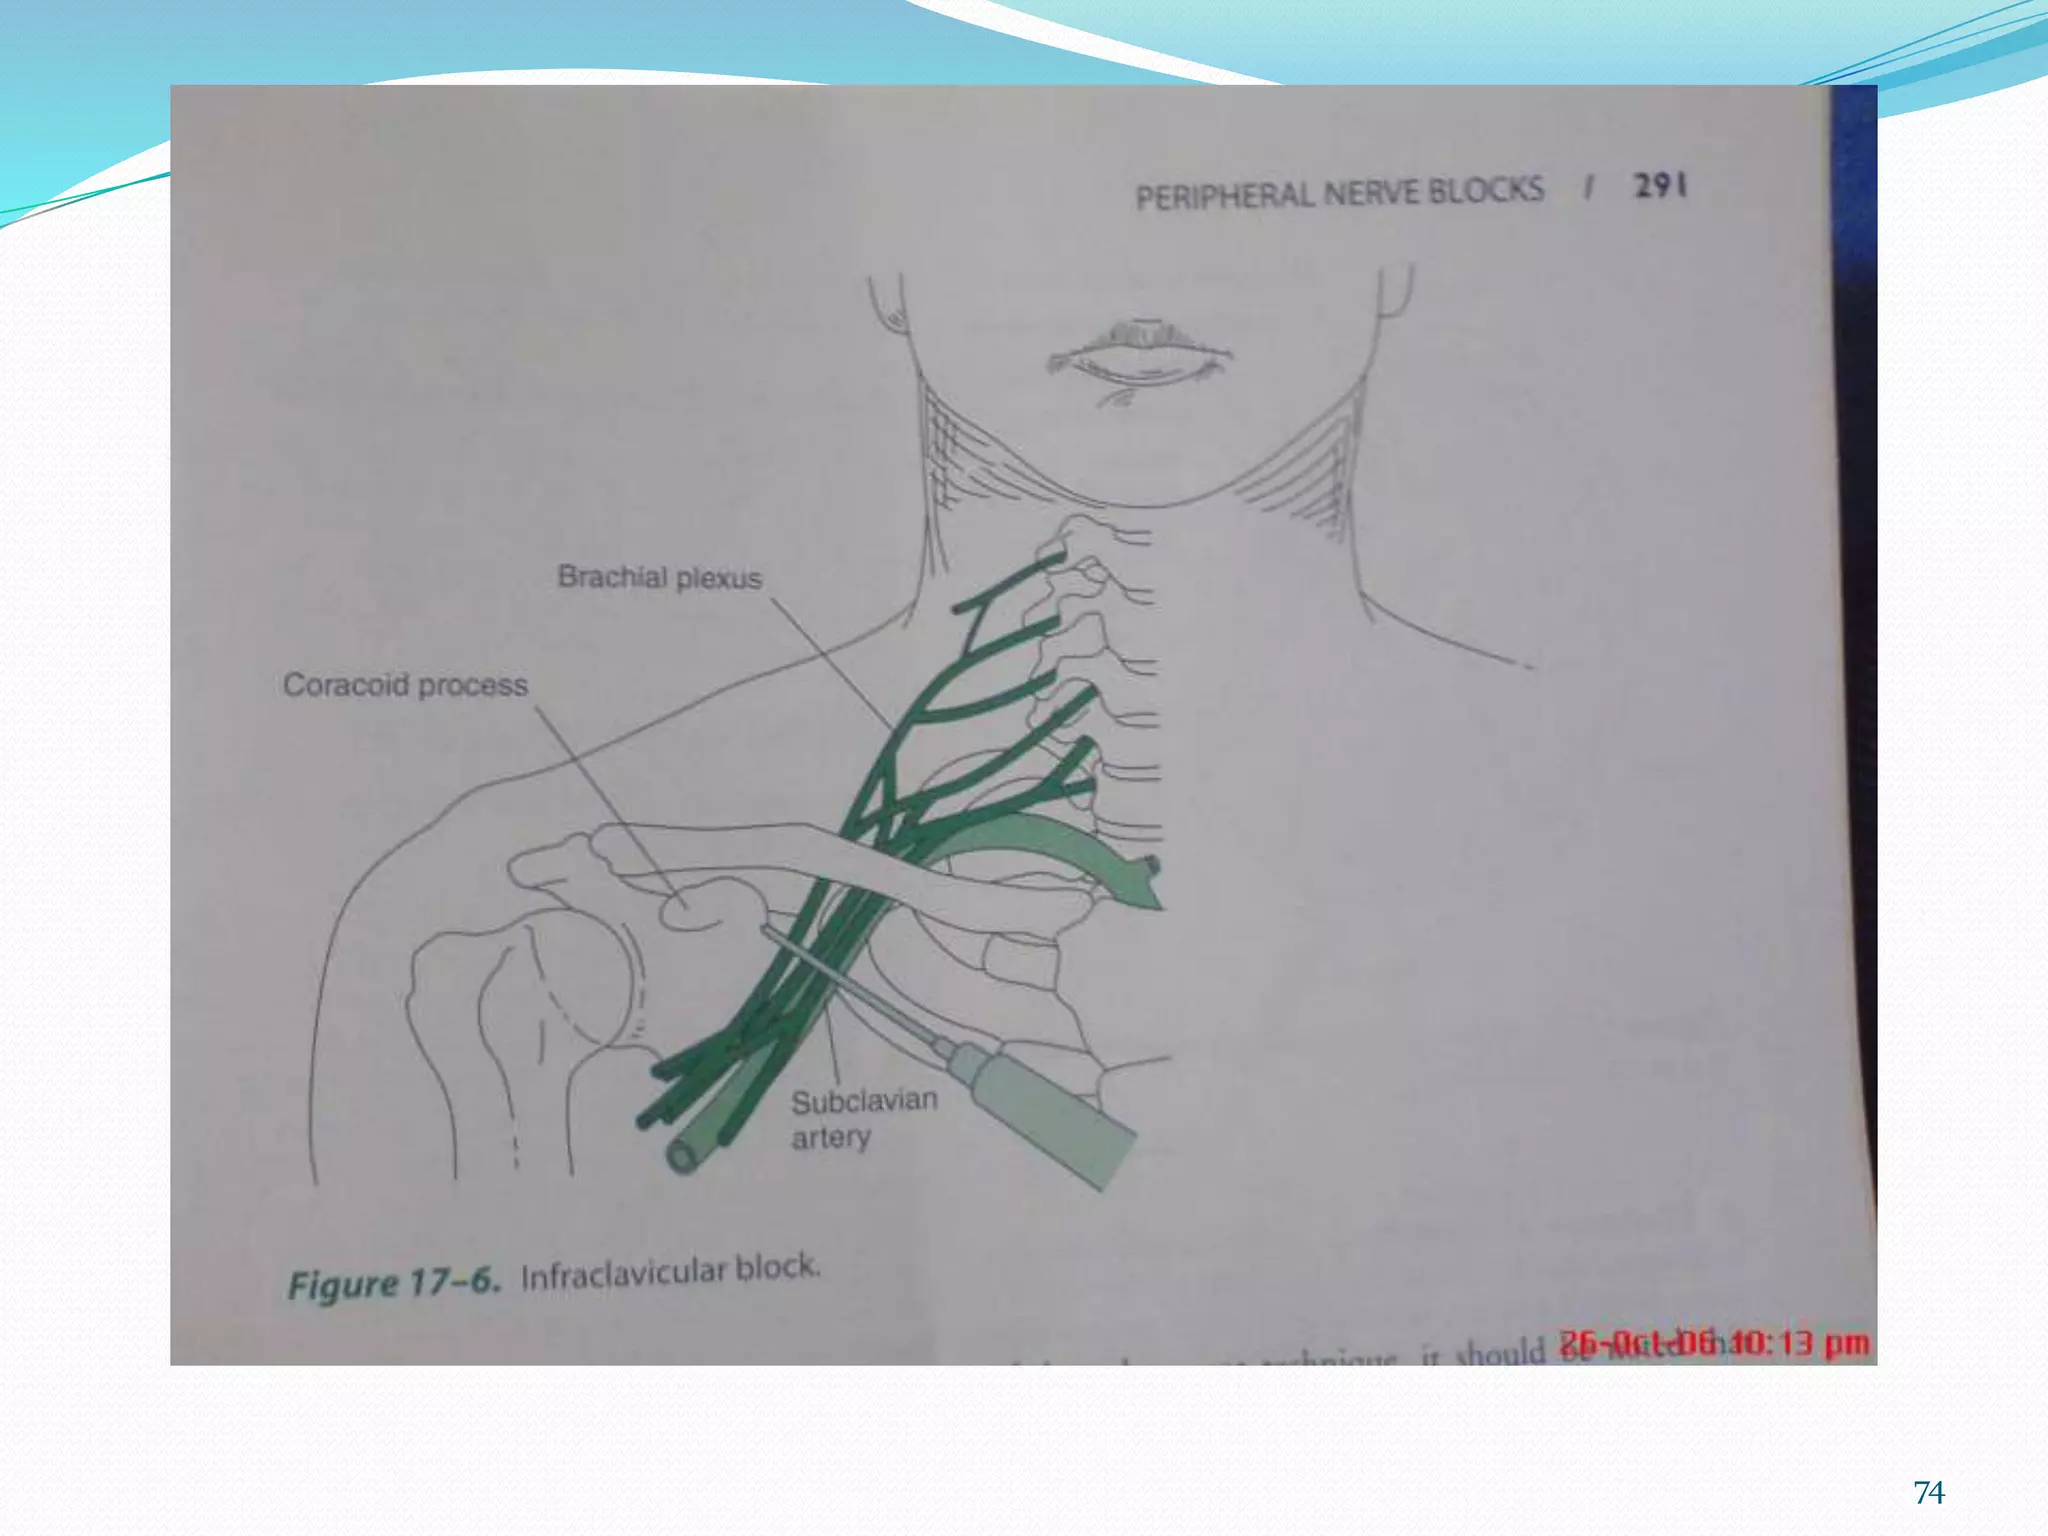

This document provides an overview of brachial plexus anatomy and techniques for brachial plexus nerve blocks. It begins with a description of the brachial plexus formation from cervical and thoracic nerve roots and its branching pattern. Four main approaches for brachial plexus nerve blocks are described: interscalene, supraclavicular, infraclavicular, and axillary. Details are provided on the anatomy and techniques for performing interscalene and supraclavicular brachial plexus blocks. Ultrasound guidance is discussed as an advancement which allows real-time visualization of needle and nerve. Complications are also summarized.